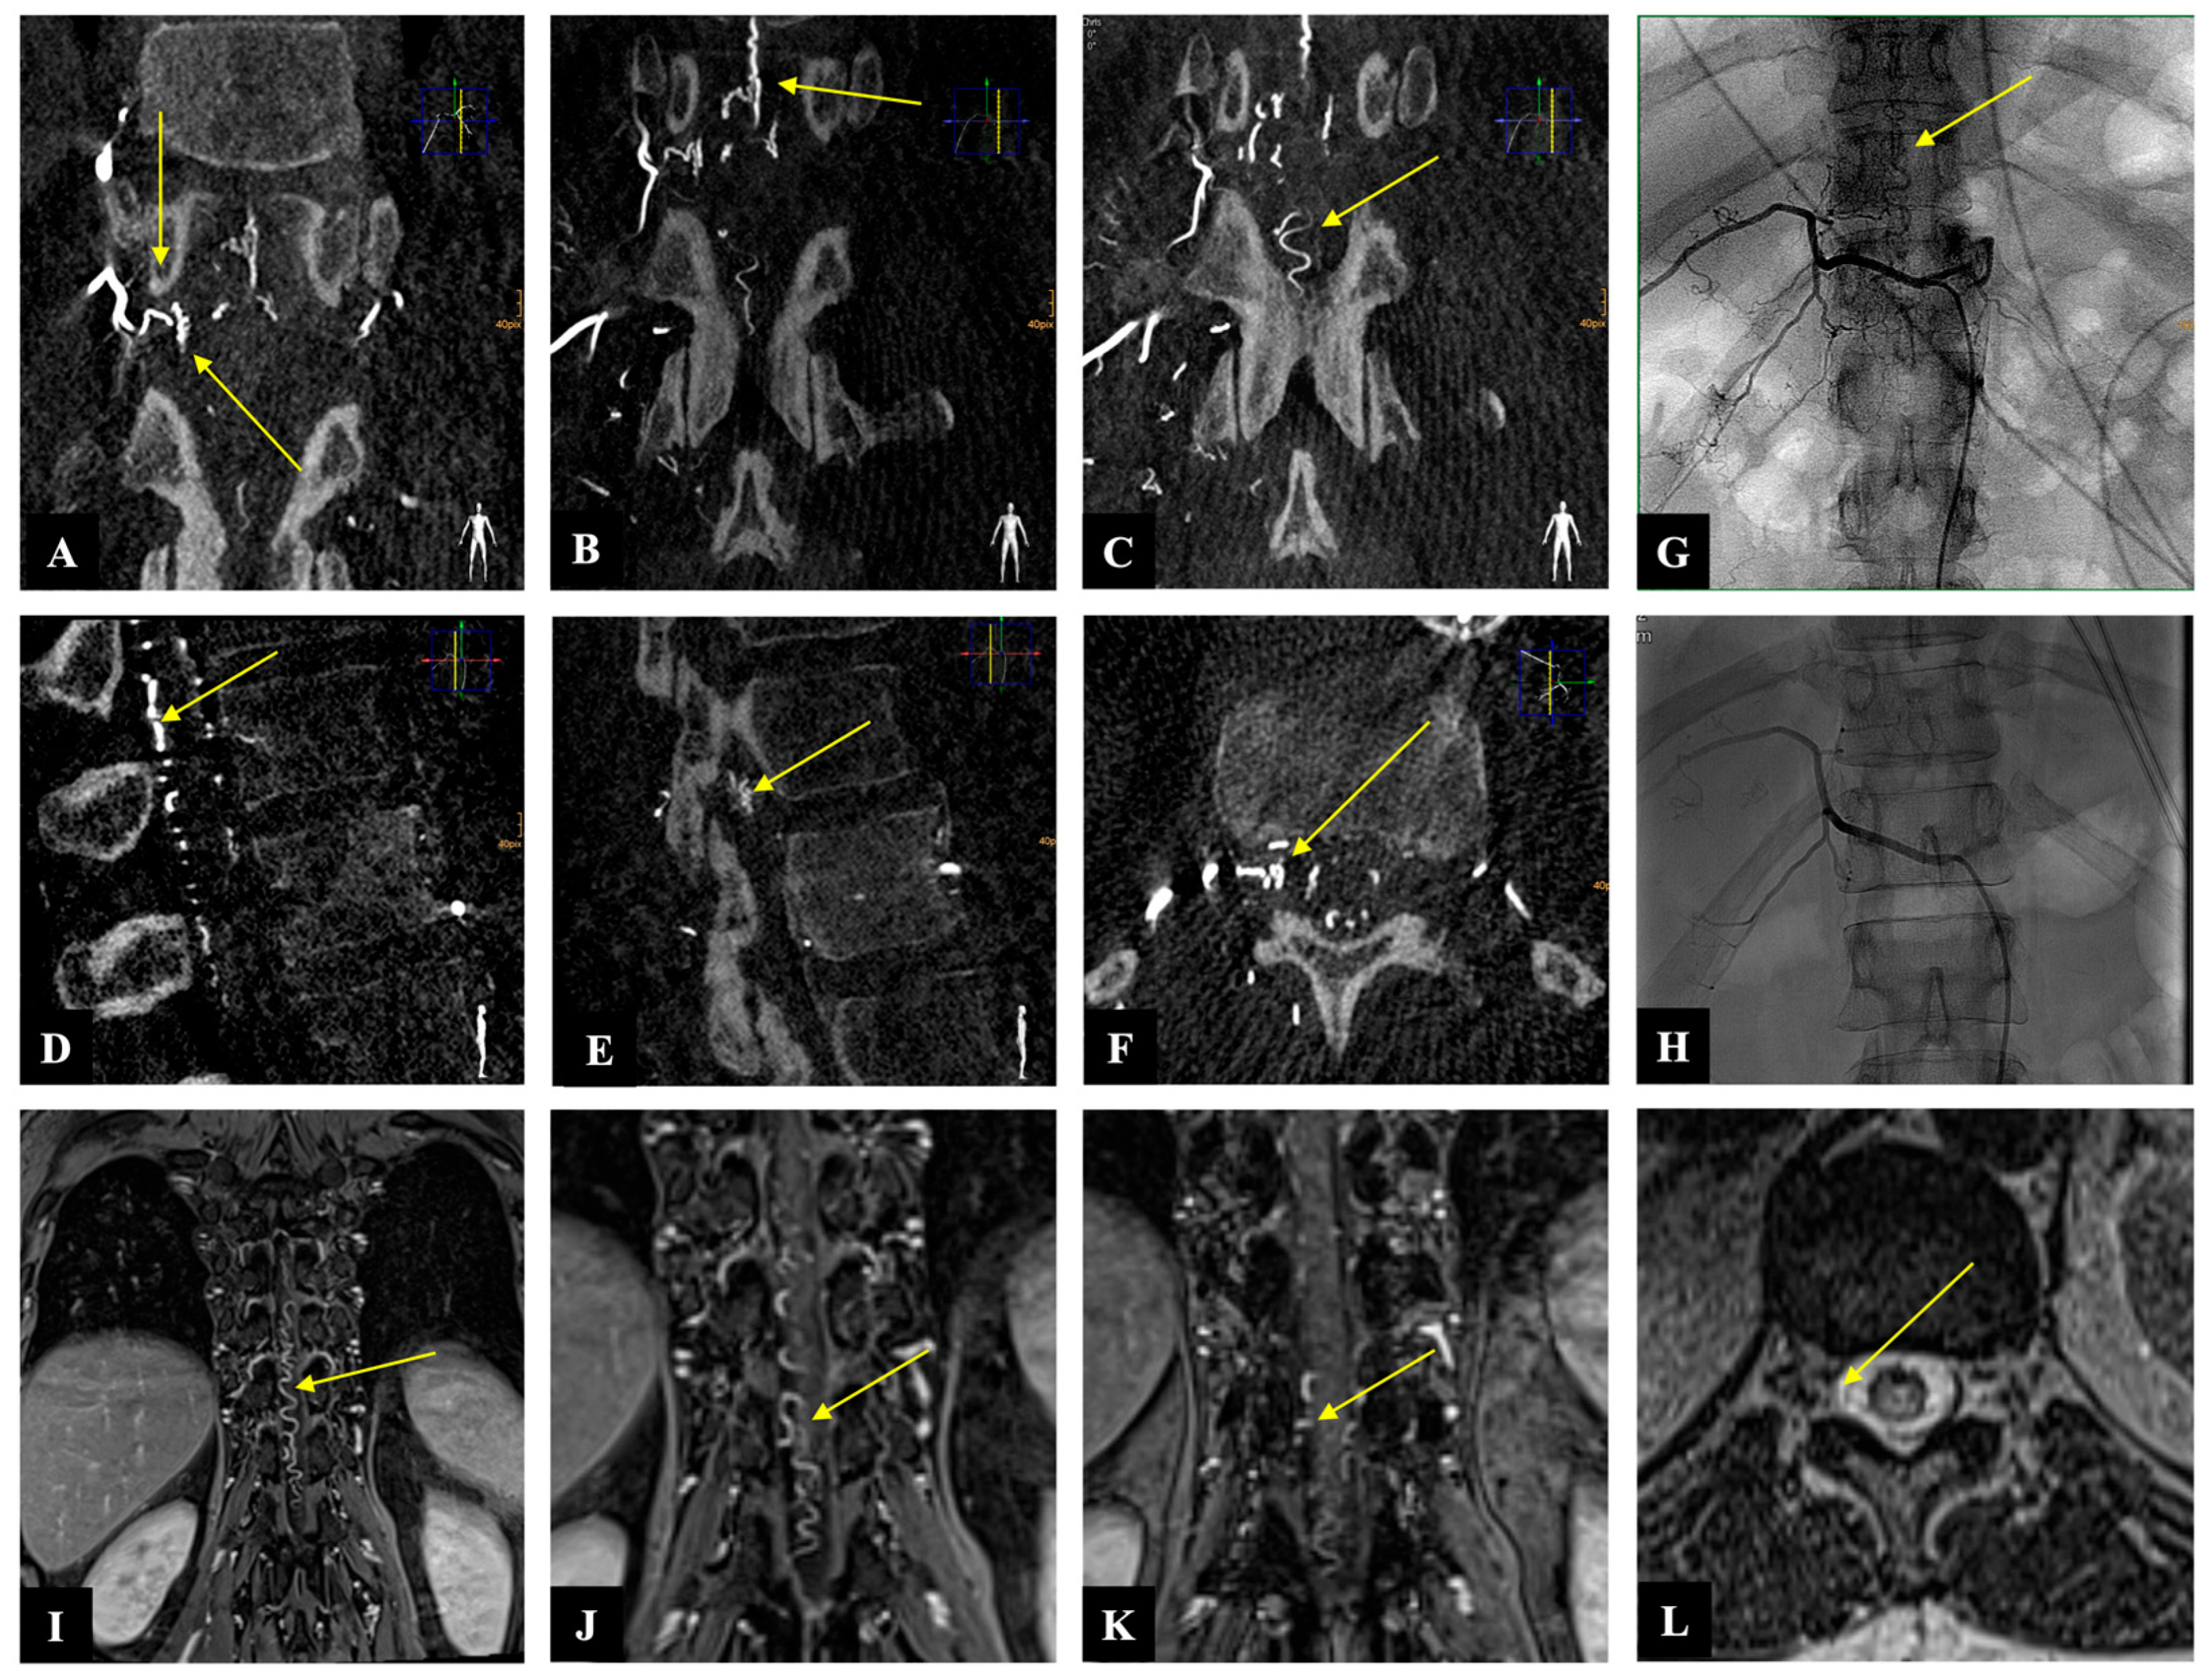

2.3. Illustrative Case

A 54-year-old woman presented with a one-month history of progressive gait disturbance, bowel and bladder dysfunction, and saddle anesthesia. The possible walking distance without a break was 200 m. There was also a slight paresis of the hip flexor and big toe extensor on the right side (ASIA-MS: 98, mALS: 6). The patient was admitted to the hospital by her general practitioner. On the day of admission, we performed a spinal MRI/MRA and DSA, which showed a DSAVF at the Th12/L1 level on the right. On the same day, the patient developed a rapidly progressing high-grade paraparesis with complete urinary and fecal incontinence (ASIA-MS: 70, mALS: 11). Emergency surgical treatment was performed via hemilaminectomy and closure of the right Th12 SDAVF without complications. Post-treatment DSA showed complete obliteration of the fistula, and MRI revealed no further flow voids and a reduction in myelopathy. The patient could be mobilized on the ward floor. After 2 months, the patient presented to the emergency room without motor deficits (ASIA-MS 100) but with a renewed deterioration of gait (gait score in mALS: 2) and persistent saddle anesthesia and leg paresthesia. The MRI showed further regression of the myelopathy and no signs of SDAVF recurrence. The gait disturbance improved spontaneously, and the patient was discharged home. At the second follow-up assessment (after 6 months), the MRI showed no myelopathy, but the patient still had a gait disturbance. A return to work was no longer possible. This case is the only one from our center with a rapid deterioration within one day, which we do not know in this form for this disease (Figure 2 and Figure 3).

Figure 3. Case illustration: The images of three-dimensionally reconstructed digital subtraction angiography (DSA) of the spine ((AC): coronary, (D,E): sagittal, and (F): axial) show the fistula location at the level of Th 12 on the right side as well as the flow voids (yellow arrows). Image (G) shows the preoperative SDAVF in conventional DSA with flow voids (yellow arrow), and image (H) demonstrates the postoperative absence of the SDAVF. The magnetic resonance angiography images ((IK): coronary and (L): axial) show the fistulous point at the level of Th 12 on the right side as well as the flow voids (yellow arrow).